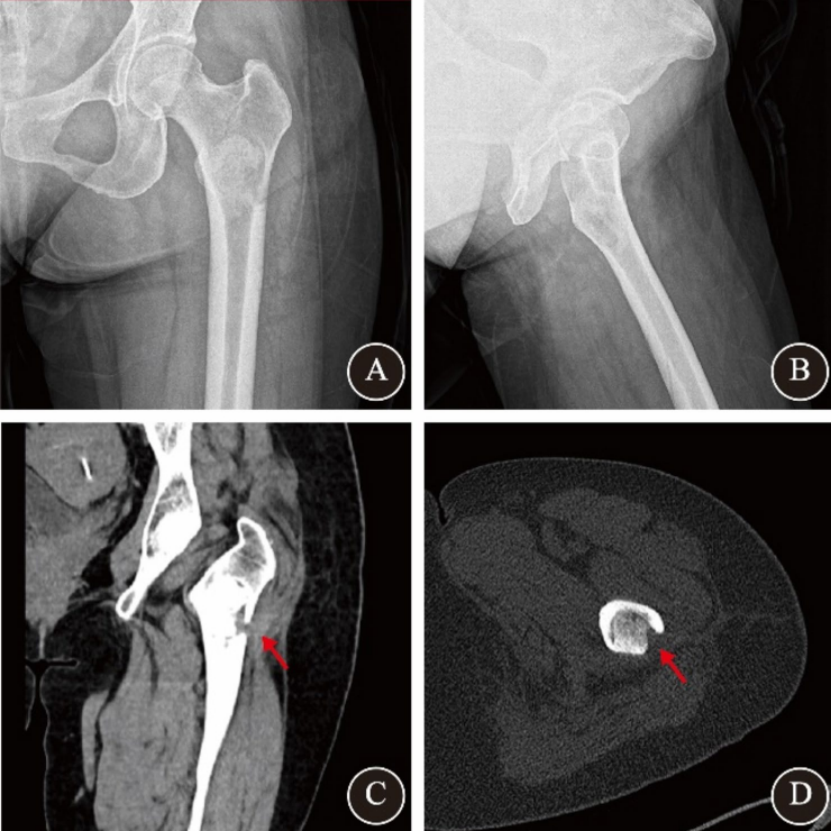

女性,49岁,检查发现发现左股骨近端占位性病变。患者无自觉症状,影像学显示左股骨近端椭圆形溶骨性病变,边界清晰,呈“磨玻璃样”改变,无皮质破坏或软组织侵犯。术前MRI提示囊性肿瘤样病变。初步诊断为良性骨肿瘤样病变。入院后广西医科大学第一附属医院脊柱骨病外科团队结合患者具体情况,制定个性化治疗方案。行AUNES辅助下肿瘤刮除+同种异体骨移植融合术。手术取左大腿近端外侧纵切口约1.5cm,透视引导下定位,逐步扩张通道,内窥镜下使用射频电极清理病灶周围组织,高速磨钻开骨窗,彻底刮除病灶后植入同种异体骨,术后病理提示骨纤维结构不良。术后第一天手术区轻度疼痛(VAS 3分),第三天出院。术后CT显示病灶腔完全被植骨填充,骨窗与肿瘤横径匹配良好。一个月随访时疼痛消失,切口愈合良好;三个月CT显示植骨融合进一步改善,无并发症发生。

图1 骨纤维结构不良患者术前影像